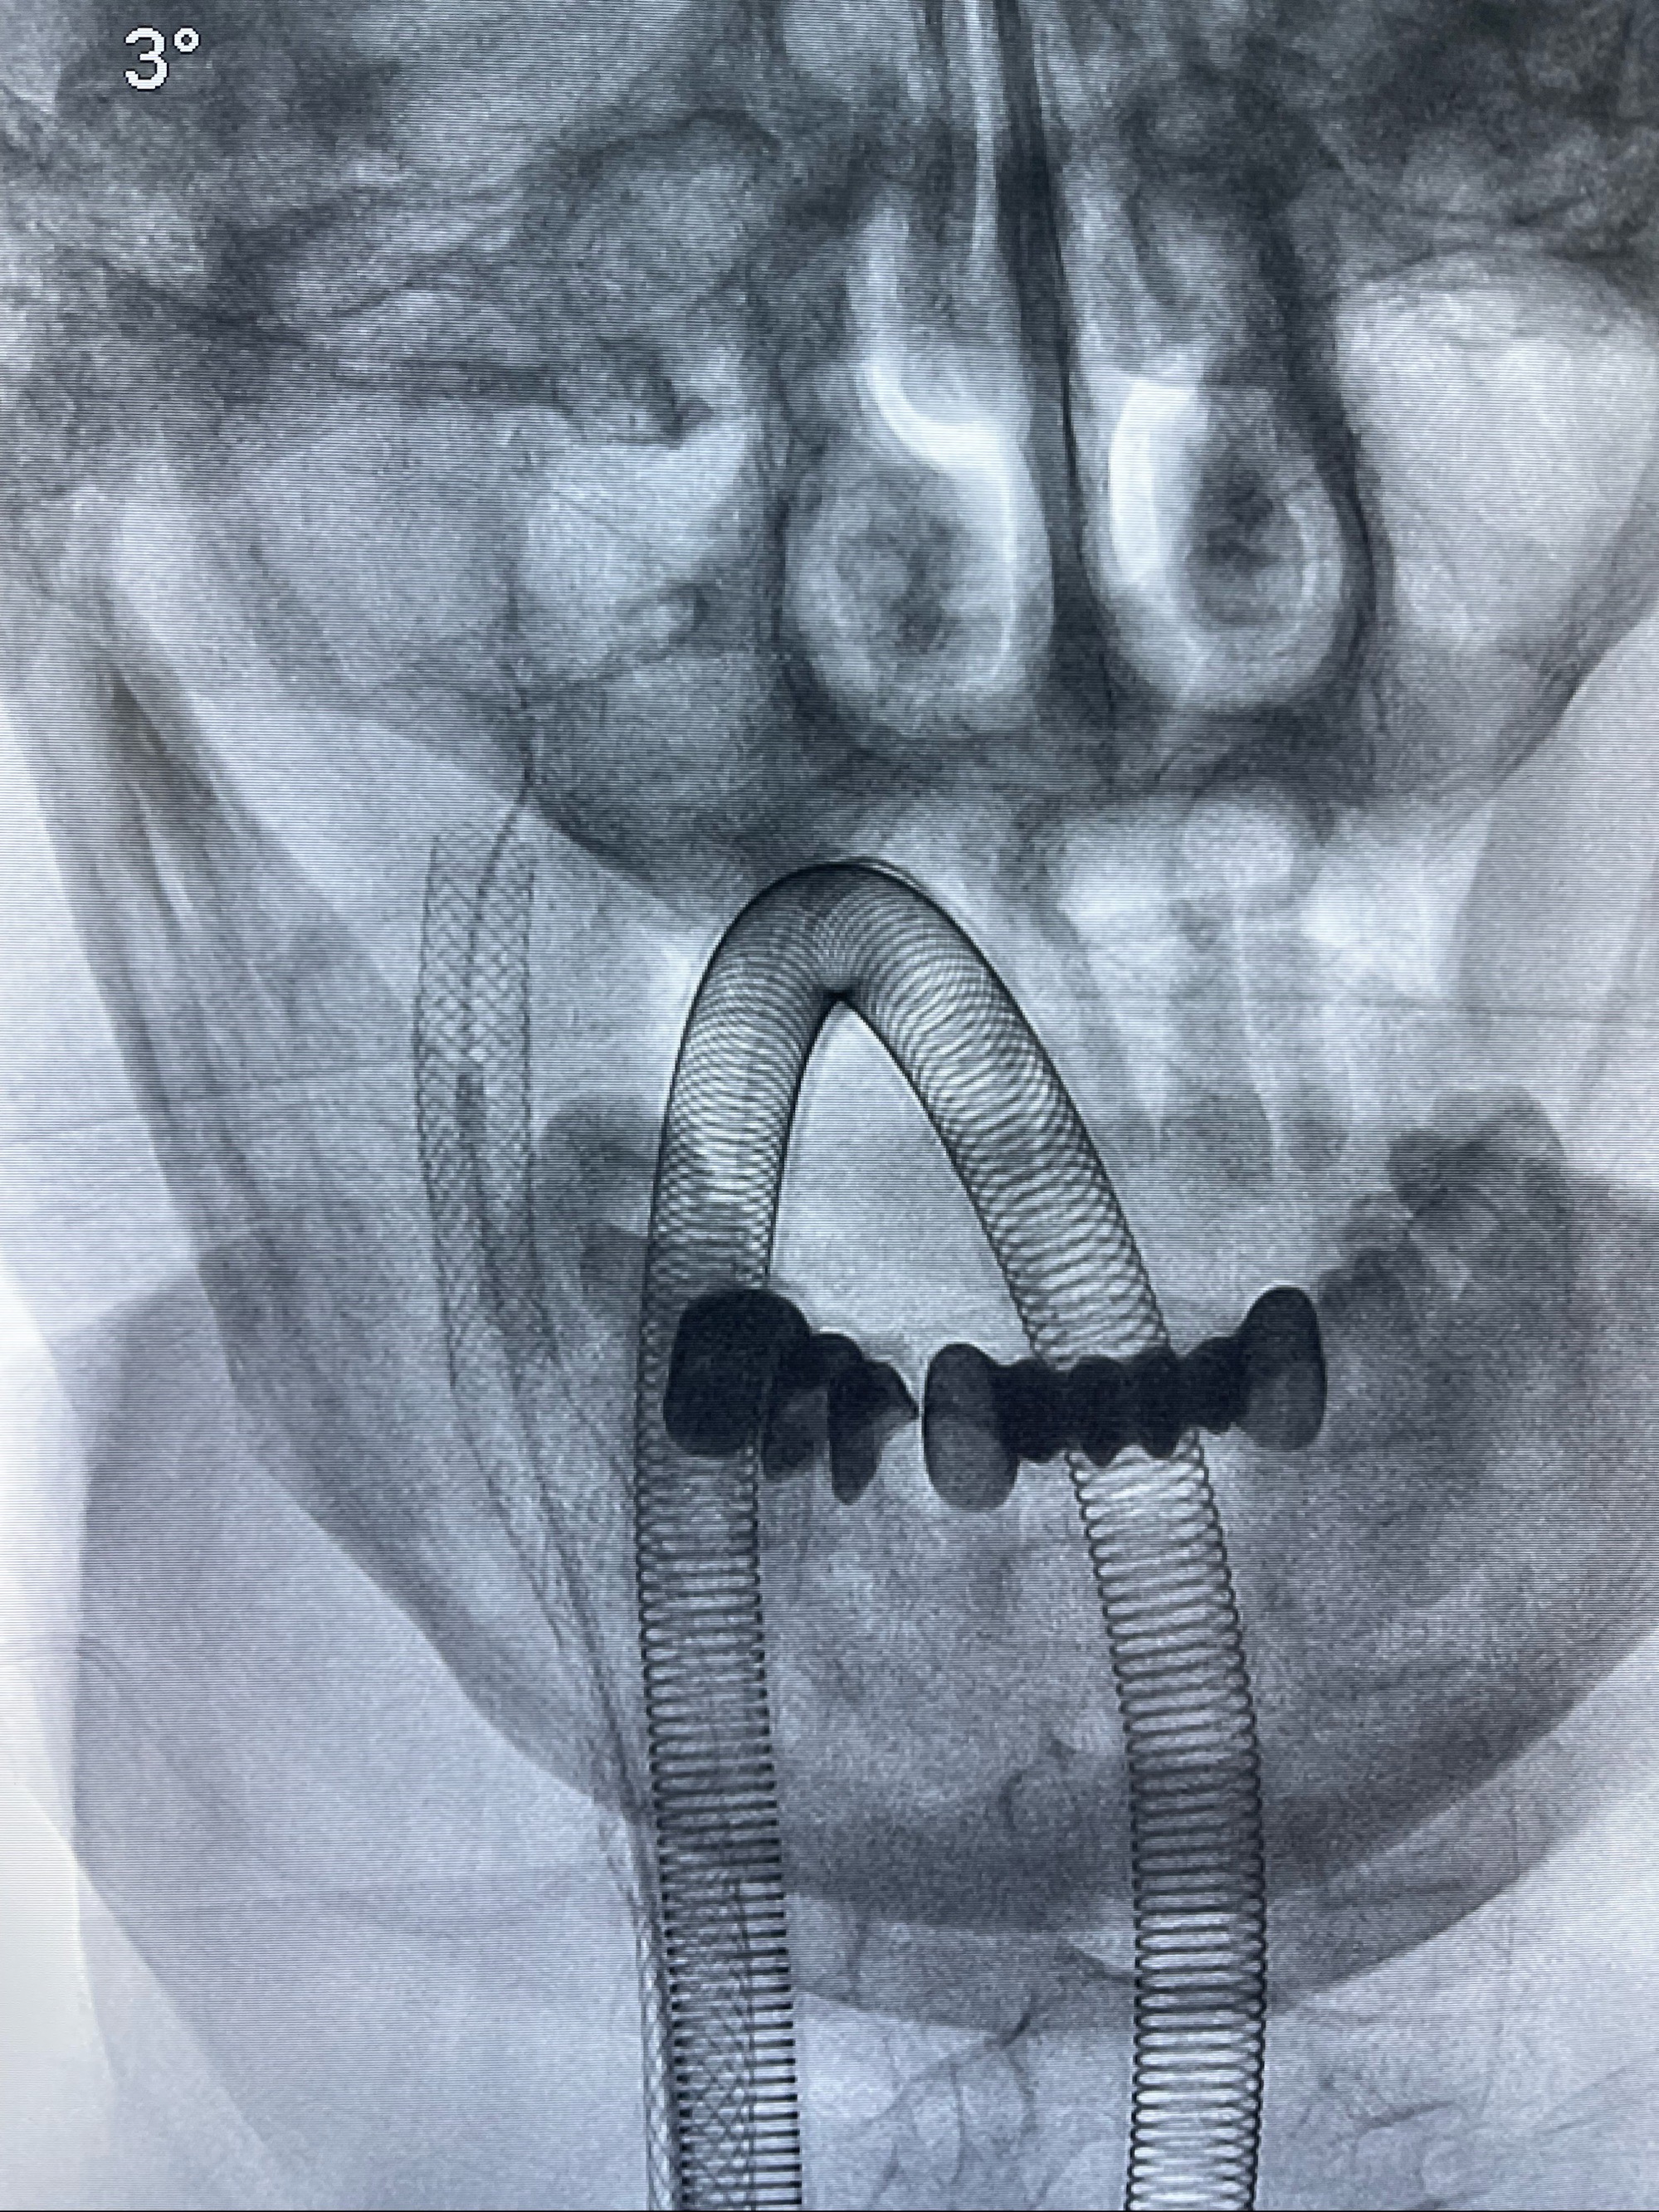

双抗准备后于2023-07-13在全麻下行右侧颈内动脉功能保护

088NeuroMAX100cm长鞘在125cmMPA及黑泥鳅导丝引导下超选择性插入右侧颈内动脉支架内

经导引导管造影显示支架远端颈内动脉不规则狭窄伴局部充盈缺损,同时行全身肝素化5ml

路径图下4-20mm球囊在导丝引导下超选择性至狭窄段,以6-8个大气压扩张,持续30s

泄除球囊造影显示局部管腔扩张佳

后移球囊至颈段狭窄段,以8-12个大气压扩张,持续30s后泄除球囊

即刻造影显示狭窄扩张佳

重新行“路径图”,支架导管在微导丝引导下超选择性插入至右侧颈内动脉眼段,4.5-50mmLeo支架释放,远心端位于海绵窦段,近心端位于岩骨段狭窄段以近

即刻造影显示支架贴壁佳

路径图下,5.5-50mmLeo支架导管在微导丝引导下超选择性插入远段Leo支架内

两枚支架部分重叠

多次确认支架位置及打开贴壁情况

支架完全打开,近心端位于原颈动脉支架远心端内